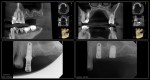

I began seeing this patient in 2014. Tooth #14 was diagnosed with a vertical root fracture at that time and the tooth was removed and the site grafted. He then presented in 2015 with a VRF of #15. It was removed and we discussed an implant in the #14 site. He did not follow up with the implant. He presented earlier this year with a vertical root fracture of #13. The tooth was removed in April and implants were placed today. Internal sinus lifts were performed for both #’s 13 and 14. I will uncover in 4 months. We have also discussed the importance of a night guard. Hopefully he will follow through with the guard. -Charles